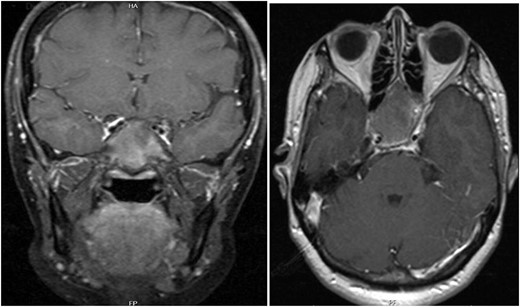

A 56-year-old female presented with a 1-year history of intermittent headaches, which had been increasing in severity and intensity over the last 2 months. The headache was mainly in the right parietal region, throbbing in nature and did not display diurnal variation. The severity of the headache was stated as 7–8 degrees on the Numerical Rating Pain Scale (NRPS; [6]). The pain was partially relieved with analgesia (acetominophen and ibuprofen). She also complained of mild right nasal congestion and intermittent mild otalgia. Physical examination was normal apart from nasal septal deviation. Computed tomography (CT) of the paranasal sinuses showed expansion of the sphenoid bone demonstrating diffuse ground-glass matrix and sclerosis obliterating the sphenoid sinus cavity (Fig. 1). Magnetic resonance imaging (MRI) was highly suggestive of fibrous dysplasia of the sphenoid bone, which appeared as expanded mass with dark T2 signal and T1 hypointense signal (Figs 2 and 3). Near-total excisional biopsy was performed using endoscopic transeptal approach to sphenoid sinuses. Histopathological examination of several pieces of greyish tan and brown bony tissue measuring 3.5 × 2.5 × 1.7 cm. showed branching irregular trabeculae of woven bone with intervening hypocellular fibrous stroma, consistent with a diagnosis of FD (Fig. 4). The patient’s headaches improved greatly following surgery. Two years post-op she reports infrequent headache with a severity of 2 on NRPS.

Different Histopathological slides confirming the diagnosis of fibrous dysplasia which presents under microscope as branching irregular trabeculae of woven bone with no osteoblastic rimming. There is intervening hypocellular fibrous stroma.